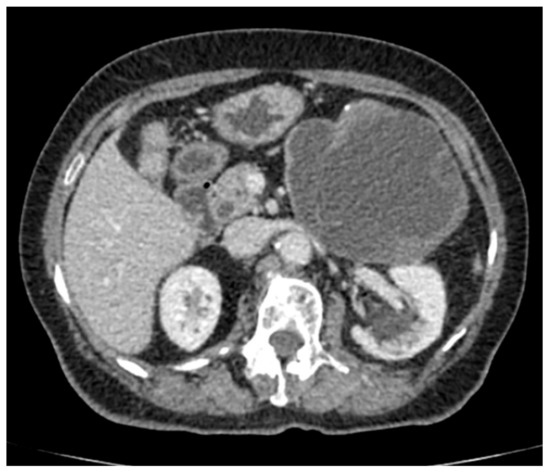

Pancreatic Hydatid Cyst Misdiagnosed as Mucinous Cystadenoma: CT and MRI Findings

2. Case Report